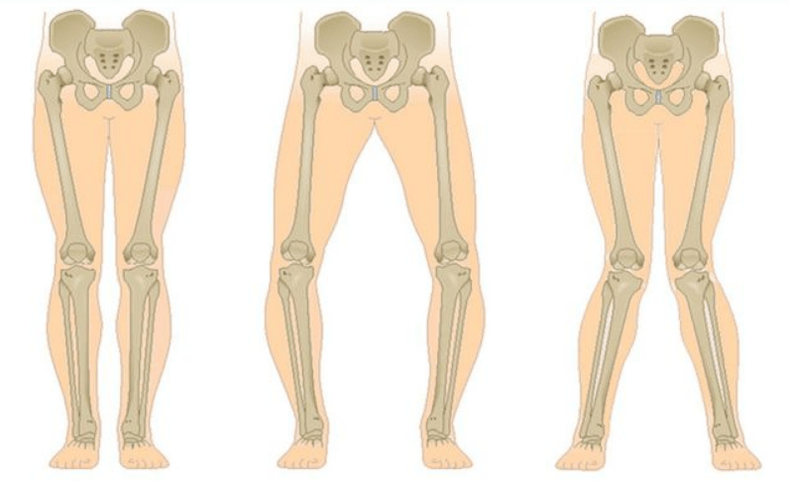

Le stade final de la gonarthrose se caractérise par le fait que la douleur devient presque constante et provoque de l'anxiété non seulement lors de la marche, mais aussi au repos et même la nuit, lorsque les patients doivent rechercher une position de sommeil confortable. Les mouvements sont plus limités : il est difficile de plier et de redresser complètement la jambe. L'articulation se déforme et augmente de volume. Une déformation en valgus (en forme de X) ou en varus (en forme de O) des jambes est souvent observée. La démarche devient instable et se dandine. Dans les cas graves, une canne ou des béquilles sont nécessaires.

Selon le nombre d'articulations touchées, on distingue la gonarthrose unilatérale et bilatérale.